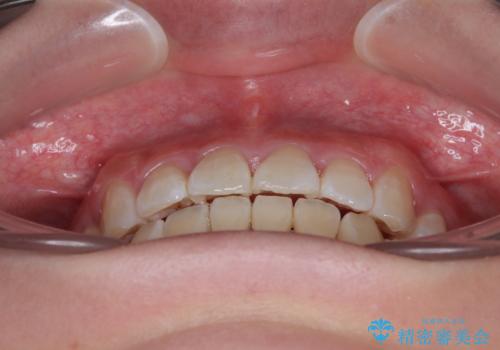

- 前歯がくちばしのように飛び出していることを気にして来院された患者様です。

唇が前方に突出している横顔が気になっているため、上下左右の第一小臼歯4本を抜歯し、ワイヤー装置にて矯正治療を行うこととしました。

わずか2年弱で一気に口元が変化し、患者様には大変満足していただけました。